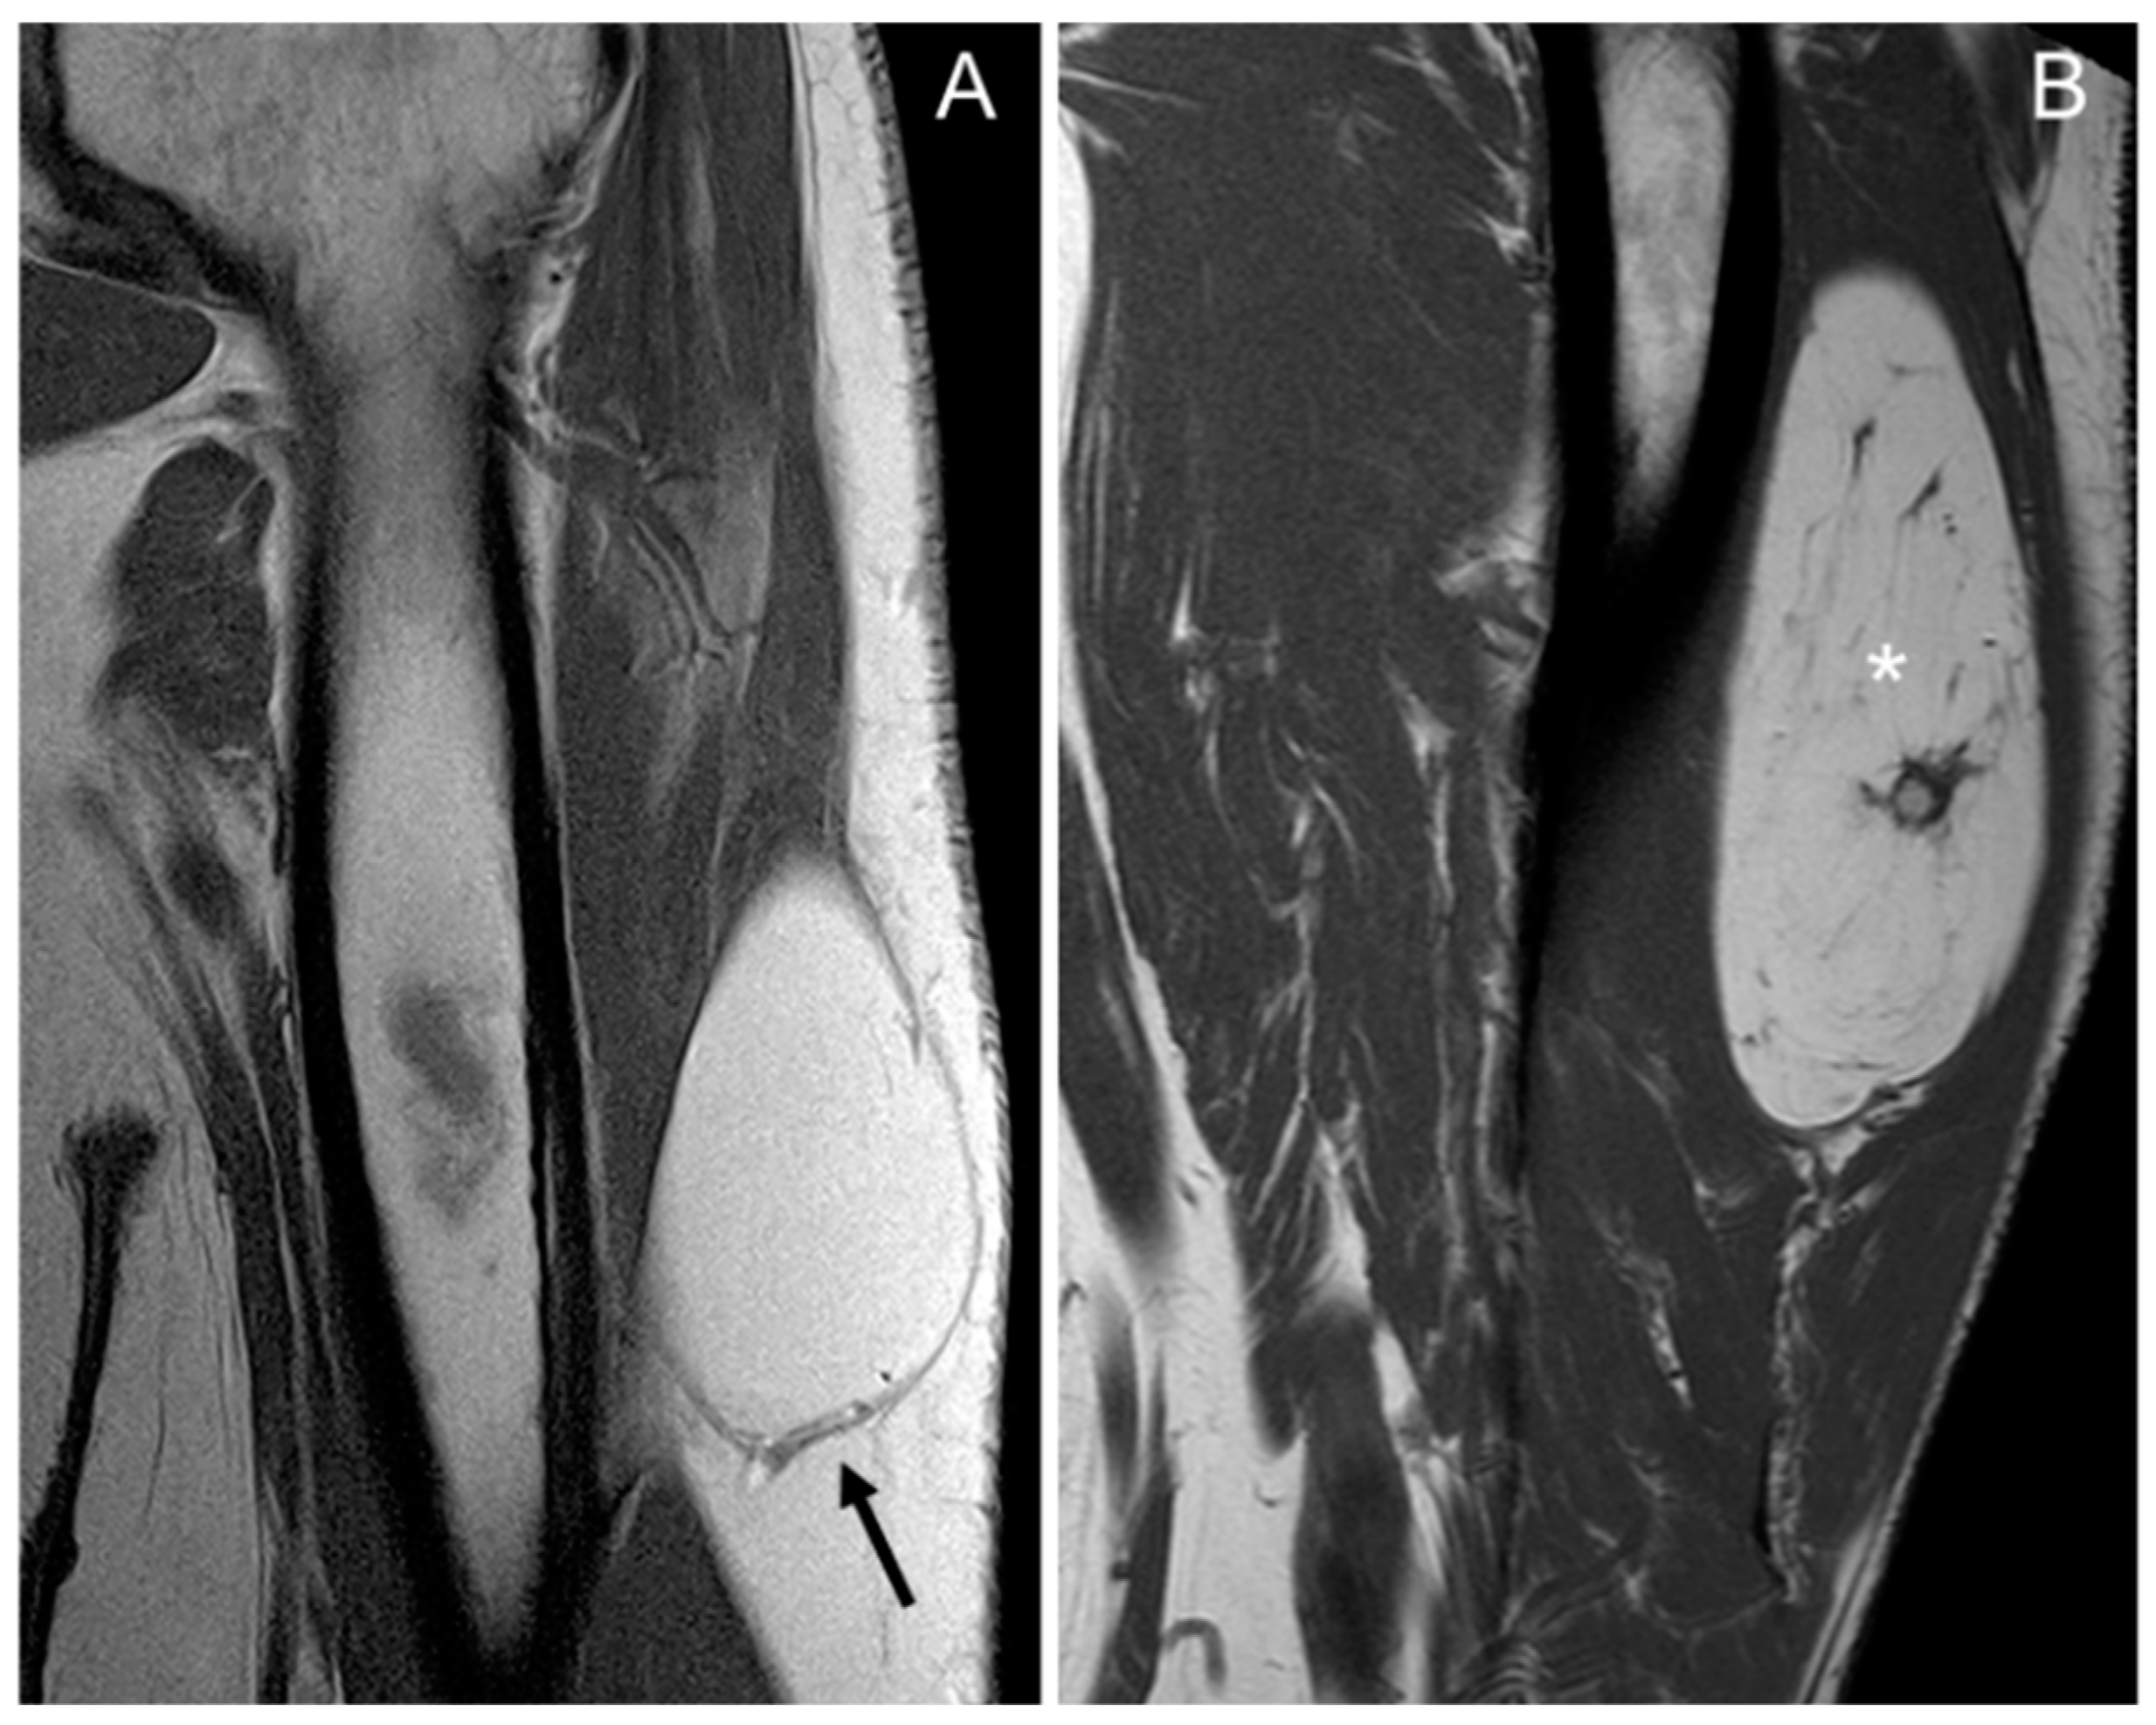

In total, 97–100% of tumors with homogeneous fat signal in the three sequences (p value < 0.001) were lipomas, and 55–61% of lesions with heterogeneous signal were lipomas (Figure 1).

Figure 1.

Coronal T1 weighted (T1W) images: (A) homogeneous lipomatous (completely fatty) tumor in the left arm (arrow), and (B) heterogeneous lipomatous mass in the left thigh, with one non-fat nodule (*) and multiple septa. The diagnosis for both tumors is lipoma, confirmed as MDM2 negative.

In our series, the lipomas showed both homogeneous and heterogenous fat signal intensity, while all ALTs were heterogenous tumors. Based on this criterion—the signal intensity of the tumor on MRI—some lipomas may be misinterpreted as ALT, but the opposite is not true; no ALTs would be misdiagnosed as a lipoma. With homogeneous hyperintensity on SE T1 and TSE T2 sequences, and complete suppression of the fat signal using fat suppression techniques, the diagnosis of lipoma can be made with high confidence. In contrast, heterogeneous tumors may be either a lipoma or an ALT (Figure 4) Therefore, homogeneous signal rules out ALT, while heterogeneous signal does not rule out lipoma (Figure 1).